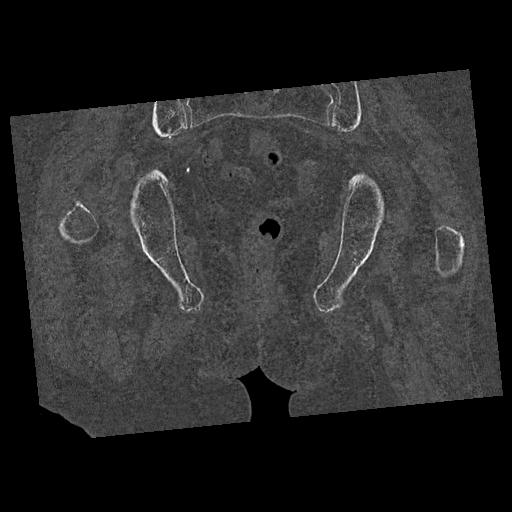

100703 1/27 両股正面+軸 1/29 両股正面+軸 94歳女性 パンソンロン